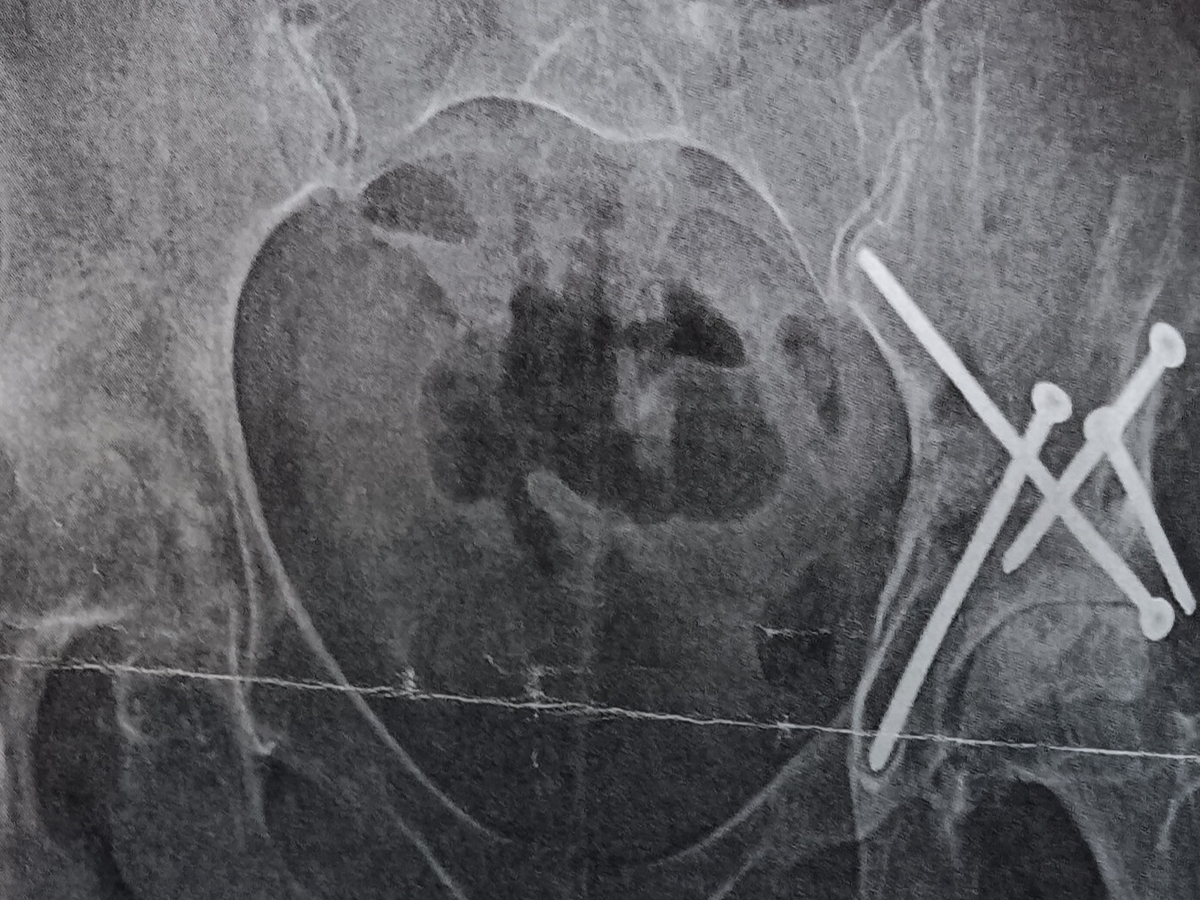

I was born with congenital hip dysplasia and underwent 9–10 surgeries before the age of 3. I thought I had left those struggles in the past — but recently, the pain returned, stronger than ever. At work, I felt a deep, grinding, breath-stealing pain in my hips that stopped me in my tracks. Soon, even simple things — putting on socks, cleaning my tiny home, driving, or walking my dog — became too much to bear.

Now I’m facing a new challenge: severe osteoarthritis in both hips, requiring surgery. The pain is constant. Work has become nearly impossible — and with it, so has keeping up with bills during my recovery.